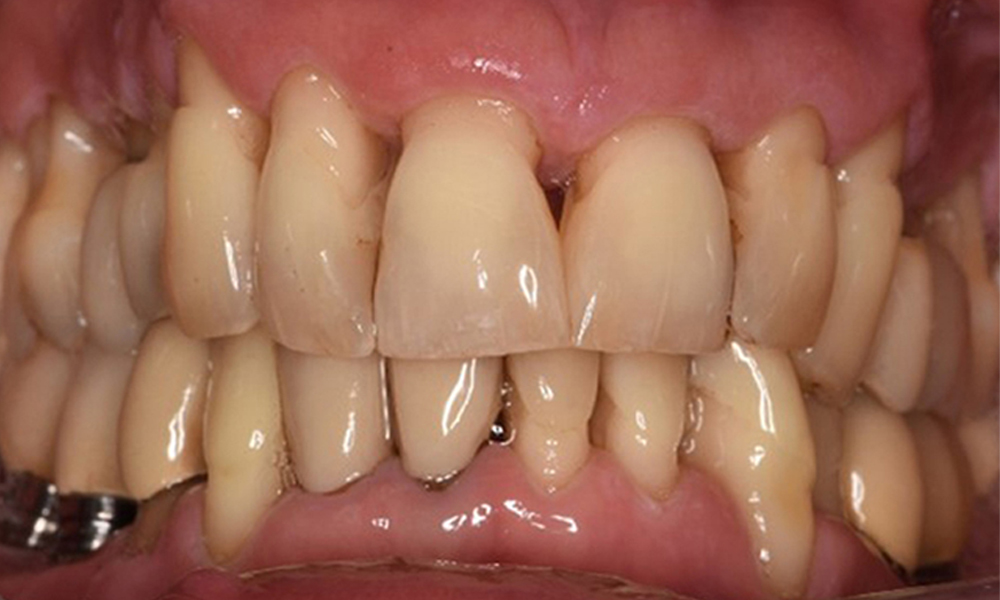

Хигиената на устната кухина и сътрудничеството от страна на пациента са много добри (виж снимката „изглед отпред“). Необходими са само повтарящи се инструкции и мотивация за поддържане на орална хигиена.

Преден изглед на зъбите (горна и долна челюст)

Изглед отпред